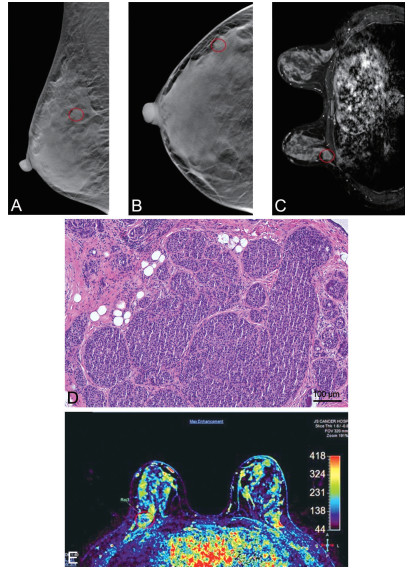

Analysis of the diagnostic efficacy of digital breast tomosynthesis in patients with early-stage breast cancer

YANG Yan, ZHAO Yunian, MAO Changfei, TANG Xiaowen, LI Dongxue

2025, 23(6): 1004-1007. doi: 10.16766/j.cnki.issn.1674-4152.004053

67 3

Abstract:

Objective  To investigate the diagnostic efficacy of digital breast tomosynthesis (DBT) in detecting early-stage breast cancer and compare its efficacy with that of magnetic resonance imaging (MRI).  Methods  A retrospective analysis was conducted on 50 patients diagnosed with early-stage breast cancer between January 2023 and December 2023. All patients underwent imaging examination, with complete and high-quality imaging data prior to pathological examination. The pathological findings were used as the gold standard to compare detection accuracy, sensitivity, and specificity DBT and MRI, as well as breast cancer staging consistency between imaging and pathology.  Results  The rates of missed diagnoses, misdiagnosis, and accuracy in detecting breast lesions for DBT were 4.00% (2/50), 6.00% (3/50), and 90.00% (45/50), respectively. Compared with MRI [2.00% (1/50), 4.00% (2/50), and 94.00% (47/50)], these differences were not statistically significant. Based on the pathological examination results as the gold standard, there was no statistically significant difference in the diagnostic results of DBT for breast cancer type classification. A total of 87 breast masses (54 malignant and 33 benign) were identified in 50 patients with early-stage breast cancer. DBT demonstrated lower diagnostic sensitivity and negative predictive value than MRI, it exhibited higher specificity and positive predictive value. Overall diagnostic accuracy was comparable between the two modalities. The cost-benefit ratio (CER) for DBT and MRI were 3.25 and 12.17, respectively, and the incremental cost-benefit ratio (ICER) for MRI relative to DBT was 713.91.  Conclusion  Digital breast tomosynthesis offers high accuracy and favorable cost-effectiveness in the diagnosis of patients with breast cancer, making it a valuable tool worthy of broader clinical application.